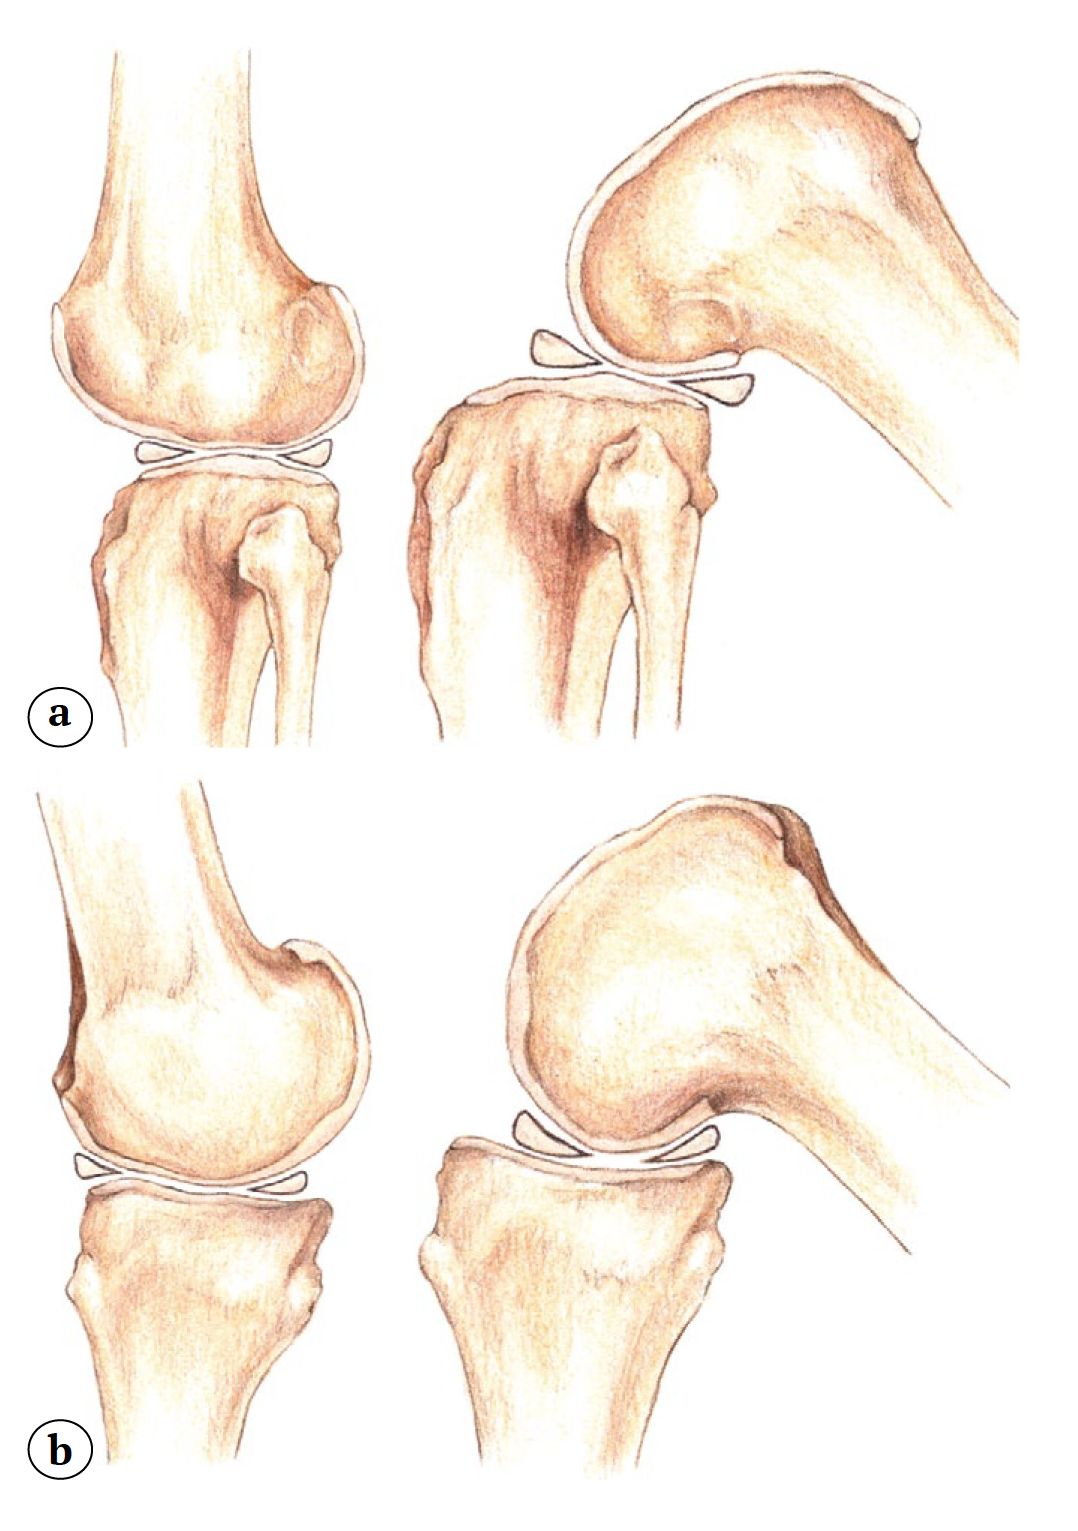

Анатомические и биомеханические особенности латерального отдела коленного сустава

С точки зрения анатомии и биомеханики латеральный отдел коленного сустава значительно отличается от медиального, что делает хирургическую технику его парциального замещения искусственным суставом высокоспецифичной. Анатомические различия медиального и латерального отделов коленного сустава включают ряд важных аспектов: различия в задних наклонах (slope) латерального и медиального мыщелков большеберцовой кости, а также разную величину их переднезаднего размера [3, 4]. Несмотря на то, что костные ориентиры латерального и медиального отделов большеберцовой кости во фронтальной плоскости расположены примерно на одном уровне, за счет хрящевой ткани латеральное плато имеет более выпуклую форму и расположено несколько проксимальнее, чем медиальное плато. Также немаловажно отметить, что латеральный мениск имеет О-образную форму, более подвижен, шире и толще С-образного медиального мениска [5]. Обращая внимание на данную особенность, O.C. Brantigan и A.F. Voshell писали: «Медиальный мыщелок бедренной кости является осью вращения коленного сустава» [6]. Под этим авторы, очевидно, понимали то, что при сгибании медиальный мыщелок бедренной кости, имея выпуклую форму и практически не смещаясь, скользит в углублении медиального мыщелка большеберцовой кости, в то время как латеральные мыщелки бедренной и большеберцовой костей имеют выпуклую форму, в связи с чем смещения наружных мыщелков костей, образующих коленный сустав, друг относительно друга, более значительны. Также важно отметить, что при сгибании медиальный мениск практически недвижим, в то время как латеральный мениск, особенно в крайних углах сгибания, значительно транслируется кзади [7] (рис. 1).

Рис. 1. Различия в мобильности латерального (a) и медиального (b) менисков коленного сустава

Fig. 1. Differences in mobility of the lateral (a) and medial (b) menisci